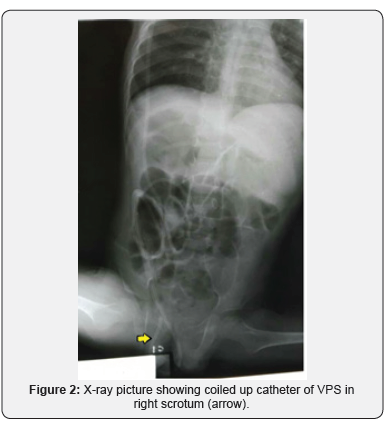

A 3-year-old boy presented with a swelling of the right inguino-scrotal region since a day prior. He had undergone right VP shunt procedure for congenital hydrocephalus at the age of 3months. The swelling was not associated with any complains of pain, fever or features of intestinal obstruction. On examination a gross swelling was noted in the right scrotal region (Figure 1). There were no clinical features of shunt malfunction. An X-ray of the abdomen and pelvis showed that the peritoneal end of the shunt coiled in the scrotum with its tip inside the abdomen (Figure 2). Patient asymptomatic of raised ICP and shunt block